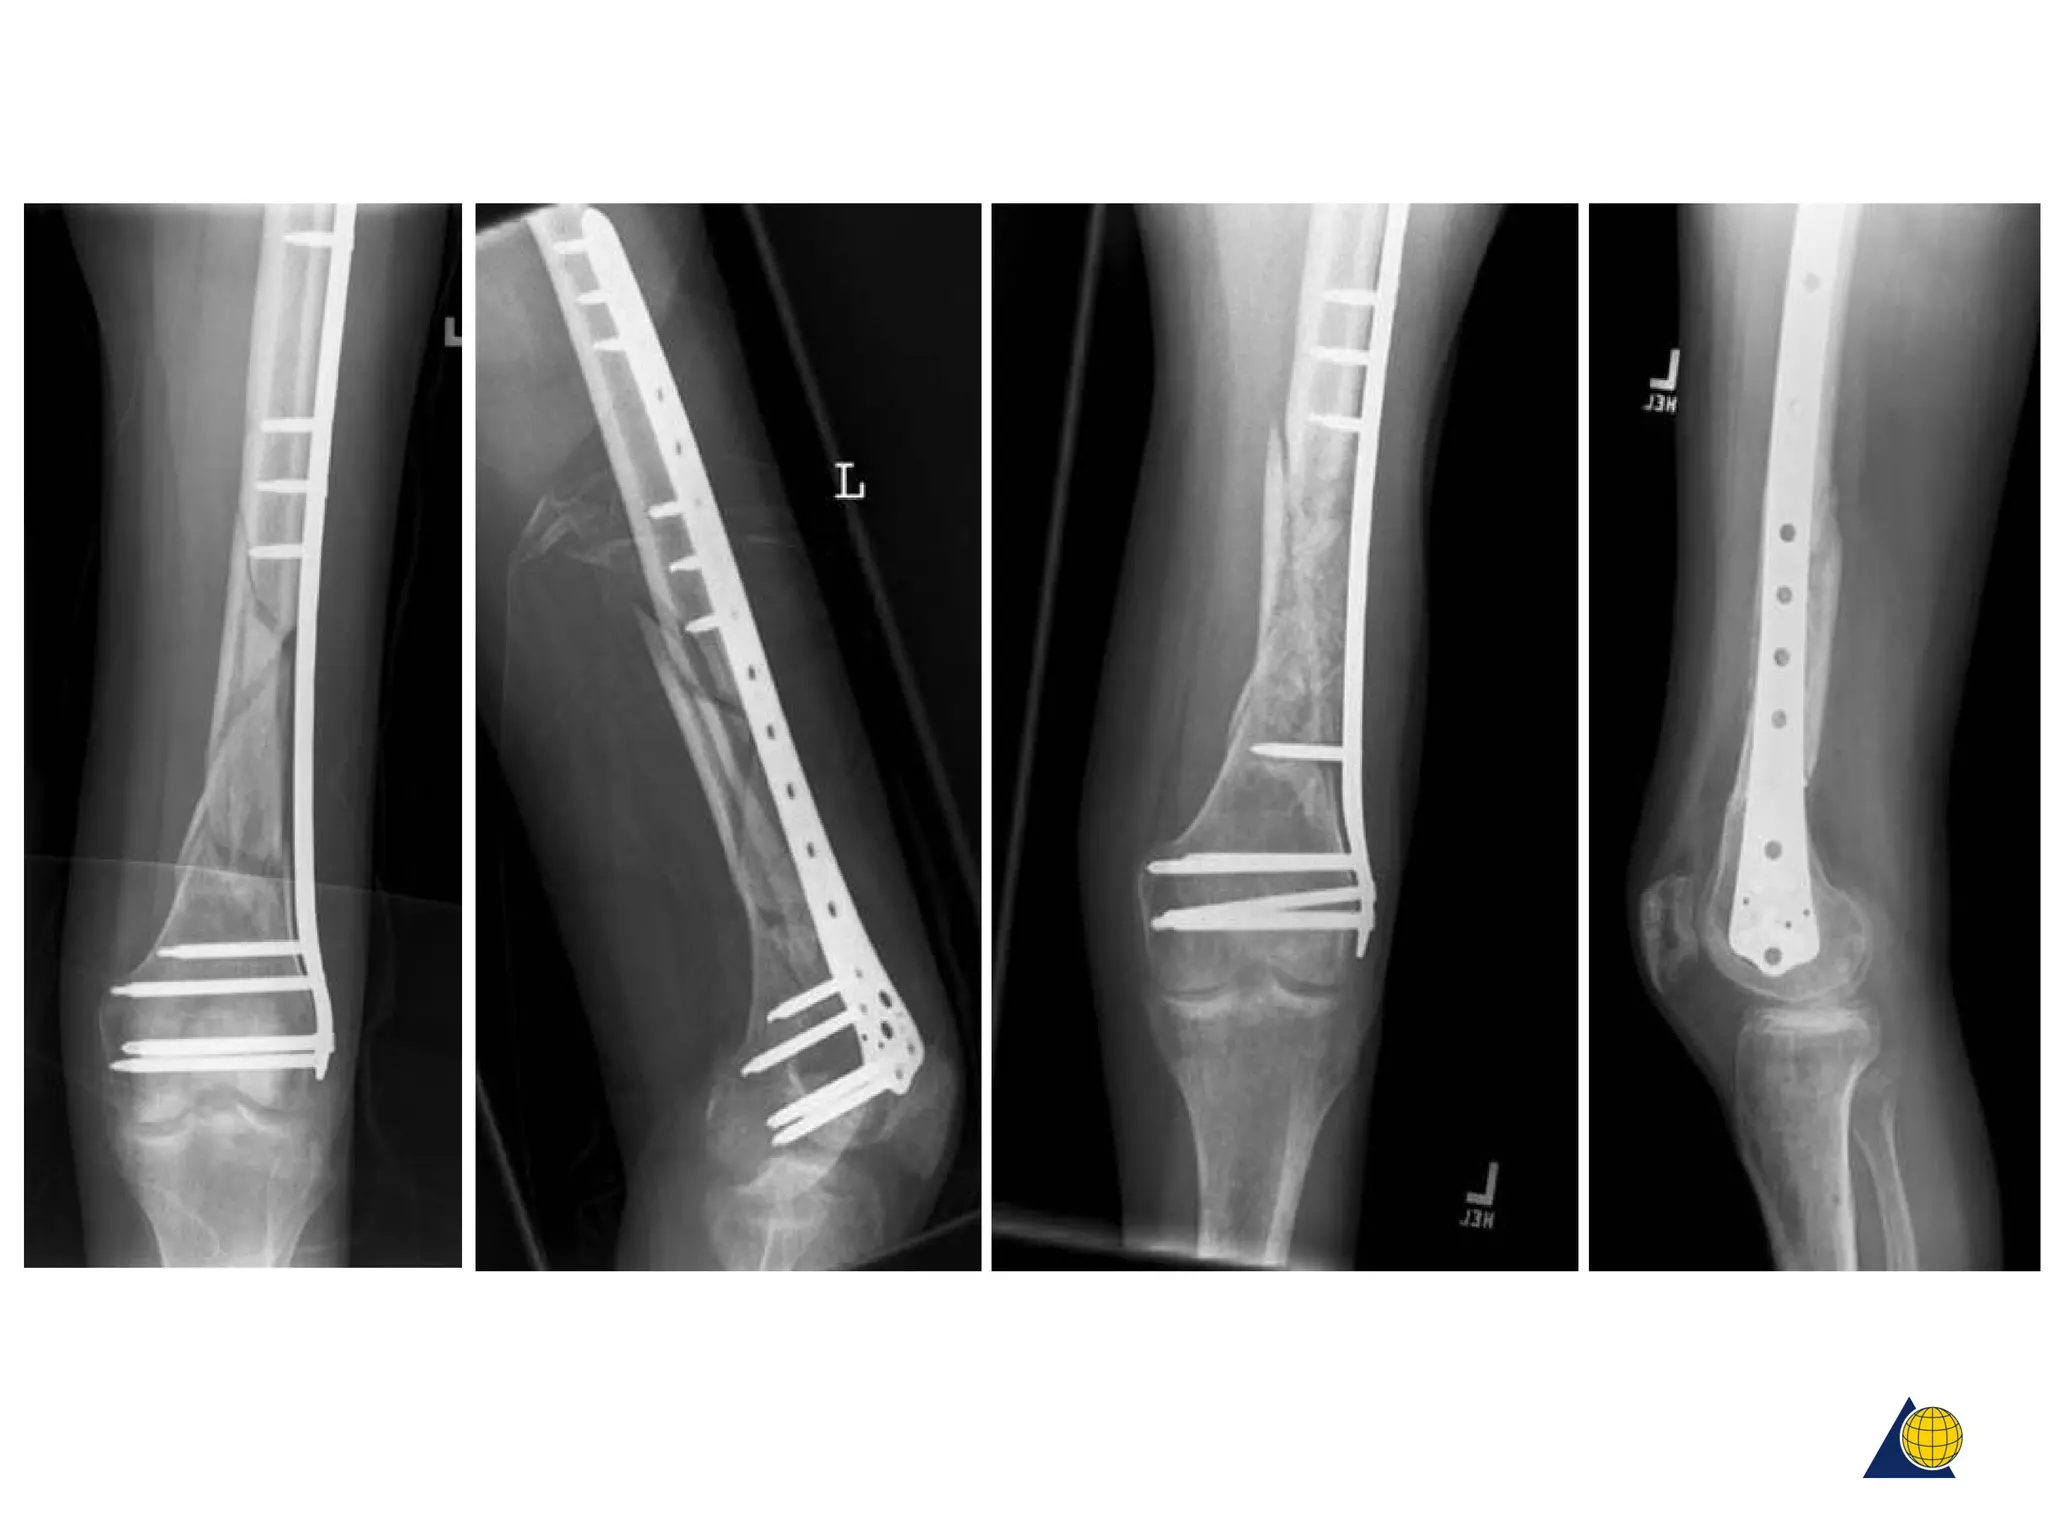

Case examples

Postoperatively 2 weeks 4 months

This Not this